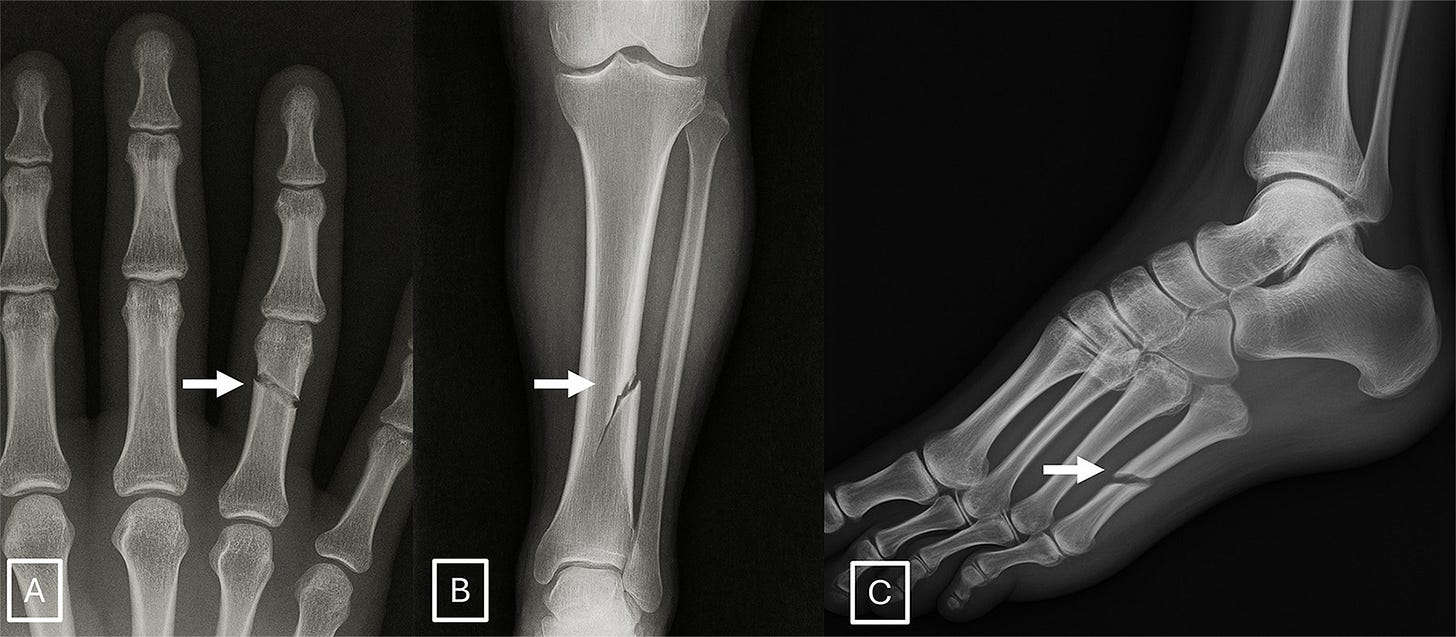

Qualitative surveying of the radiologists after the initial phases of the study indicated certain features were more suggestive of synthetic radiographs: absence of noise, overly-smooth cortex, and unnatural-appearing fracture patterns. A few examples: